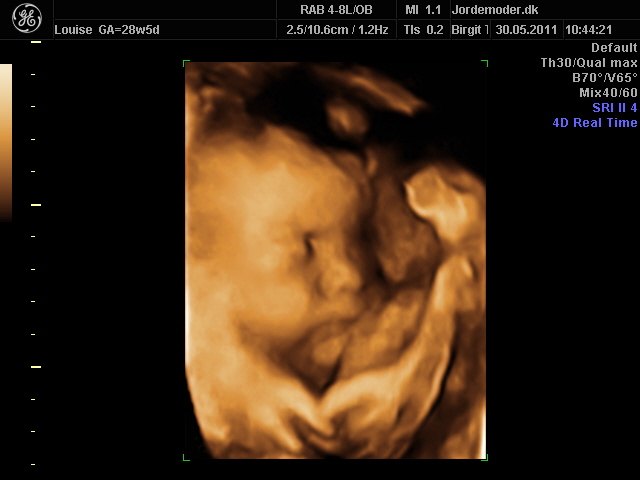

Moar2011

i uge 28

Vedhæftede fotos (klik for at se i fuld størrelse)